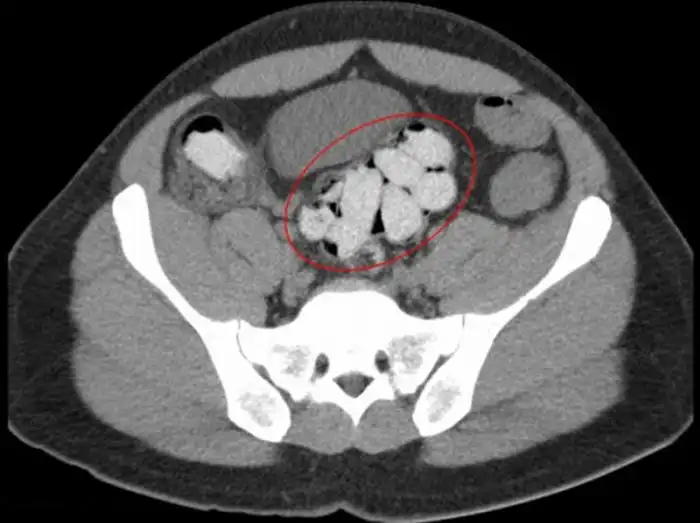

20 контейнеров с наркотиками в толстой кишке

Эти цветные пакетики наркотиков находятся в толстой кишке

Наркотики в толстой кишке